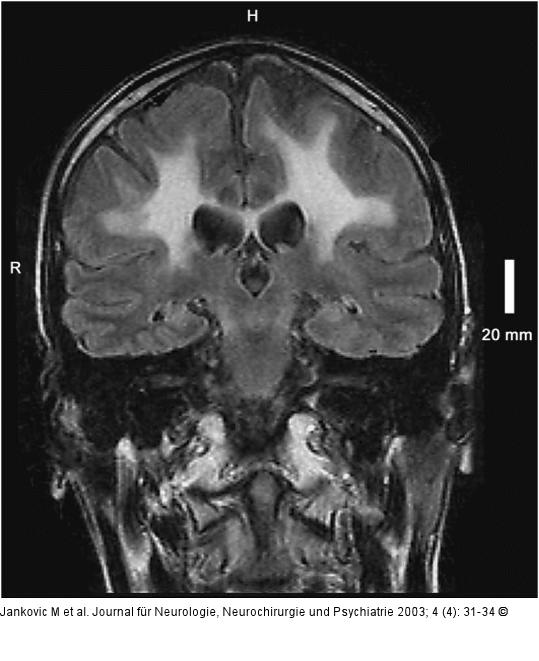

Abbildung 2: Adrenomyeloneuropathie Koronale TIRM: Ausdehnung der Hyperintensitäten bis zur Subkortikalregion. |

Koronale TIRM: Ausdehnung der Hyperintensitäten bis zur Subkortikalregion. |